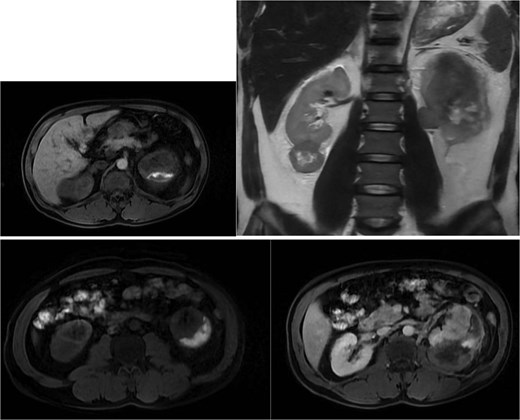

Abdominal magnetic resonance imaging (MRI) showed approximately seven to eight right renal masses (largest 32 × 35 × 37 mm) and five to six left renal masses (largest 62 × 55 × 55 mm). The renal lesions were iso- to mildly hypointense on T1-weighted imaging and mildly hypointense on T2-weighted imaging, without macroscopic fat. Post-gadolinium images demonstrated heterogeneous enhancement with central necrosis in the dominant masses (Fig. 3). Diffusion-weighted imaging showed marked restriction in the viable tumor components (Fig. 4). The dominant left renal mass, located in the mid kidney, demonstrated invasion of the posterior renal fascia. Subacute hemorrhage under the left renal capsule measured up to 24 mm in thickness.

Diffusion-weighted imaging (b = 800) and ADC maps showing restricted diffusion in the viable components of bilateral renal tumors.